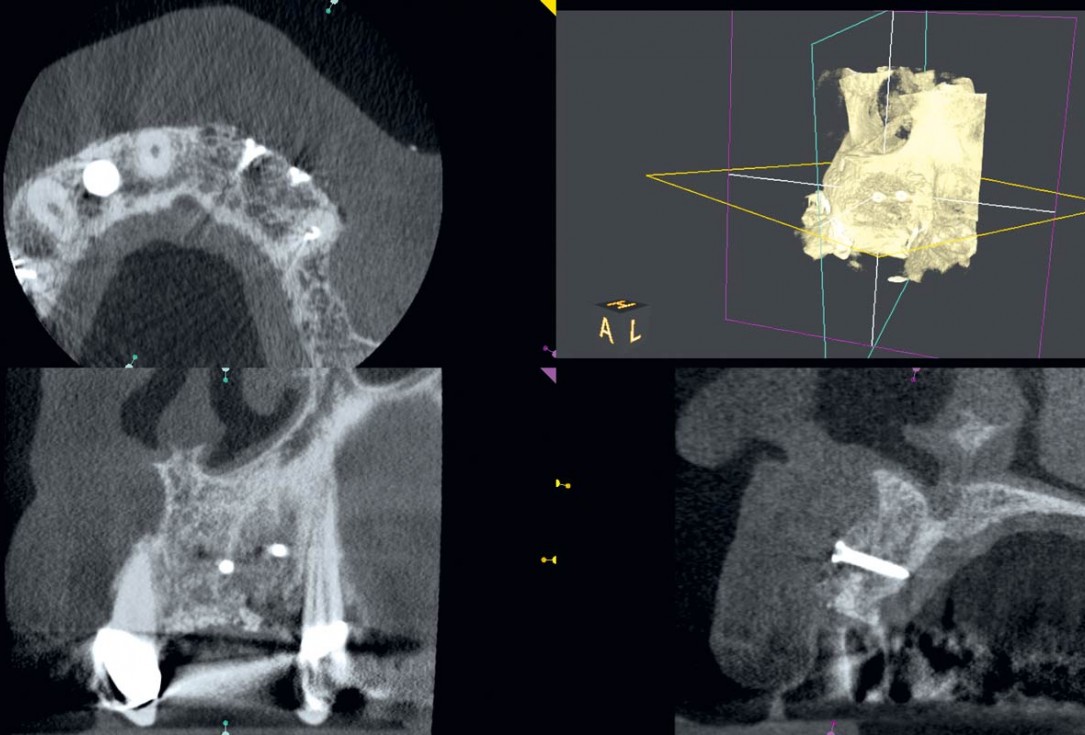

5/14 - Radiological situation after removal of prostheticsAugmentation in the aesthetic zone with maxgraft® bonebuilder – PD Dr. Dr. F. Kloss